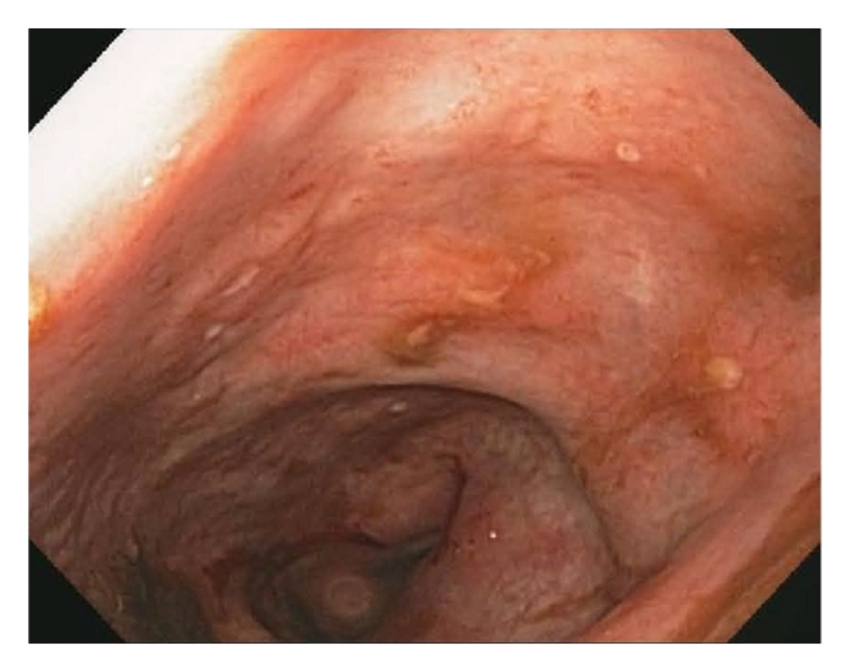

Auf der Grundlage dieser hämatologisch-instrumentellen Daten werden endoskopische Untersuchungen (Gastroskopie und Koloskopie) und die Bestimmung von Calprotectin (positiv getestet mit einem Wert von 72 g/kg) durchgeführt. Aufgrund der typischen Läsionen, die zunächst bei der Koloskopie und später bei der histologischen Untersuchung der Dickdarmschleimhautbiopsie festgestellt wurden, konnte die Diagnose Morbus Crohn gestellt werden.

Endoskopische Merkmale von Morbus Crohn. Bildnachweis5